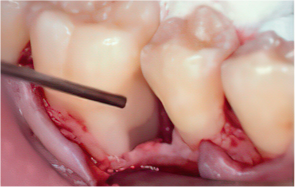

엠도게인 수술과정

-

STEP 01

잇몸을 절개

STEP 02

Scaling Root Planning을 실시

STEP 03

치석 및 치태 등 제거